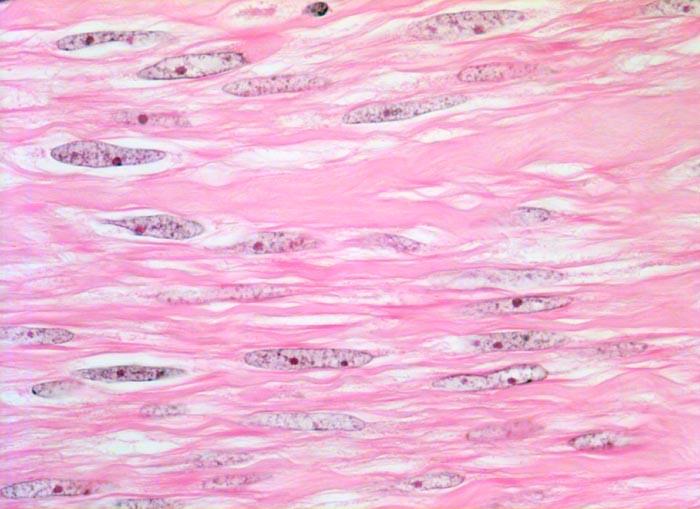

Myome imponieren makroskopisch typischerweise als runde, scharf begrenzte und nicht bekapselte Knoten. Die Schnittfläche ist weiss mit wirbliger Struktur. Mikroskopisch ist der Tumor aufgebaut aus Bündeln (=Faszikeln) spindelförmiger Zellen mit reichlich dunkel-eosinophilem Zytoplasma und an den Enden abgerundeten länglichen, zigarrenförmigen Kernen. Zell- und Fasergehalt sind sehr variabel. Degenerative Veränderungen wie Verkalkungen (> 4280), hyaline Nekrosen, Einblutungen, Homogenisierung des Kollagens, Ödem oder myxoide Degeneration und Zystenbildung (> 4279) kommen häufig vor. Manche gutartigen Leiomyome können ein einzelnes Malignitätskriterium aufweisen (vermehrte Mitosen, hohe Zellularität, deutliche Zellatypien oder Nekrosen). Falls mehr als eines dieser Kriterien vorhanden ist, handelt es sich differentialdiagnostisch um einen leiomyomatösen Tumor mit unsicherem Malignitätspotential (STUMP=Smooth Muscle Tumor of Uncertain Malignant Potential) oder um ein Leiomyosarkom. In seltenen Fällen lässt sich die Dignität nicht sicher bestimmen.

Morphologische Merkmale:

• Zwei scharf begrenzte Knoten im Myometrium bestehend aus Bündeln glatter Muskulatur.

• Variabler Anteil Fibrose (Kollagenfasern).

• Glatte Muskelzelle: eosinophiles Zytoplasma, längliche Kerne mit abgerundeten Enden (zigarrenförmig).

• Keine signifikanten Zellatypien. (signifikant=bereits in der Übersichtsvergrösserung erkennbar).

• Keine Mitosen.

• Keine Tumornekrosen.